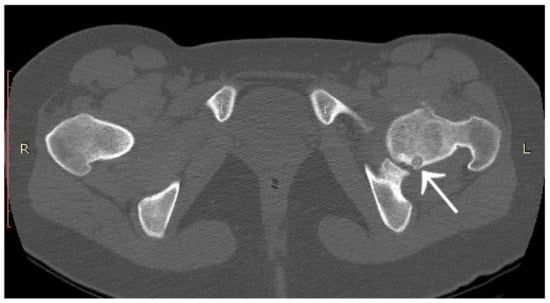

3.1. Case 1: OO Masking as Femoroacetabular Impingement (FAI)

3.6. Case 6: OO Masking as Chronic Hip Arthritis